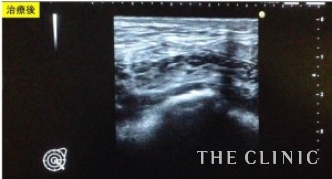

脂肪の塊を吸引しました。白くゴロゴロした塊はなくなっていますね。

このようにしこり1つ1つ、エコーで確認しながら治療をしていきます。